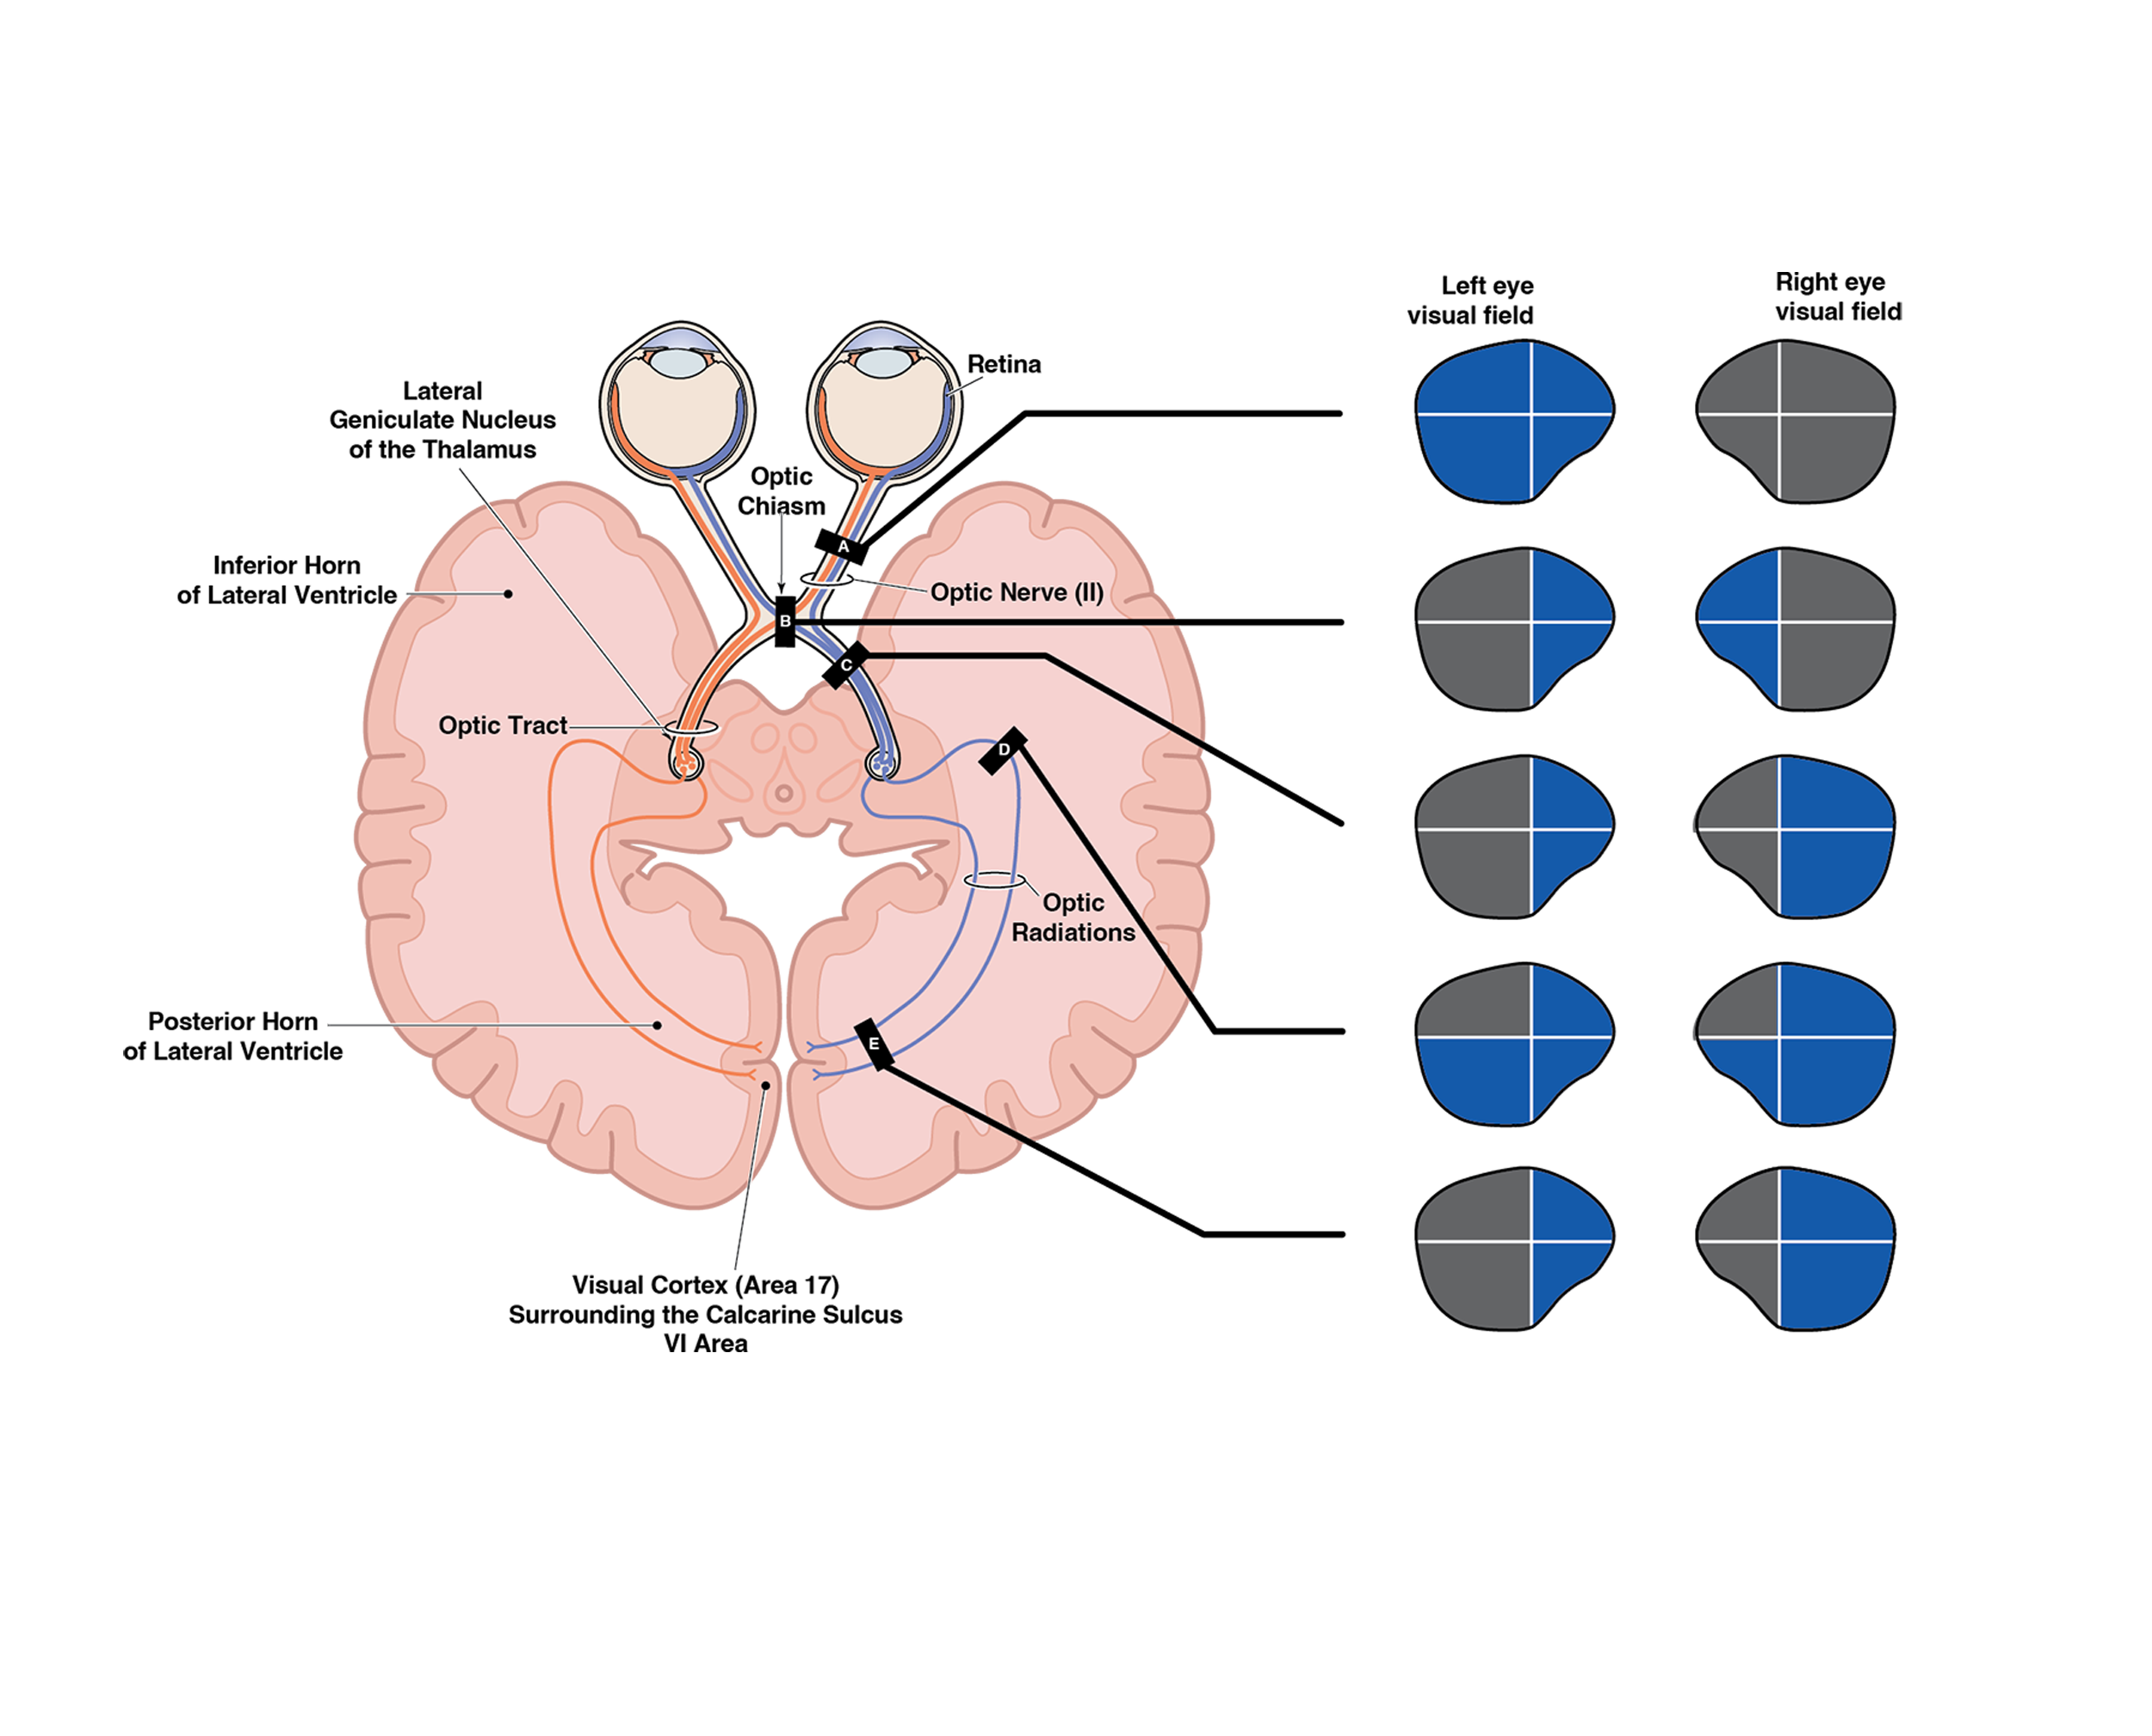

Informative, straightforward illustrations can help patients better understand their medical condition, treatments and procedures. Doctors and healthcare providers can use illustrations to communicate more effectively and reduce a patient’s anxiety about their condition or treatment.

Instructional illustrations are used to teach or explain medical information to a specific target audience. Examples include;

Publications including textbooks and journals.

Surgical illustrations visually depict operative techniques, surgical anatomy, and complex procedures. They are created with high anatomical accuracy and serve as a visual bridge between complex surgical knowledge and learners, clinicians, or patients.